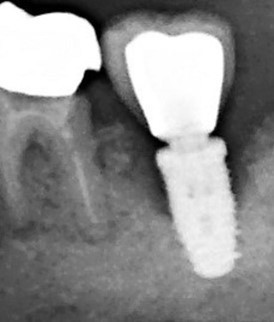

Au stade de « péri-implantite » il s’agit d’une atteinte inflammatoire des tissus mous entourant un implant. Le diagnostic clinique comprend un saignement au sondage, avec une suppuration quasi systématique, et une profondeur de poche péri-implantaire supérieure ou égale à 5 mm. Radiographiquement, un aspect radioclair de déminéralisation osseuse marginale supérieure ou égale à 2 mm entoure une partie plus ou moins étendue du corps de l’implant (fig 1 et 2).

Figure 1: suppuration au sondage d’une molaire atteinte de péri-implantite

Figure 2: aspect radiographique de la perte osseuse confirmant la péri-implantite